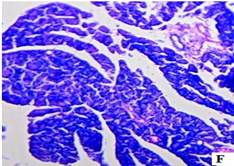

The histopathological studies of the pancreatic tissues are shown in (fig. 3). Normal rats showed the normal architecture of the pancreas with the preserved islet of Langerhans cells (fig. 3A). Induction of diabetes using Streptozotocin resulted in hyalinization of islets of Langerhans cells with focal mild degenerative changes, mild fibrosis, dilated and congested vessels along with focal chronic inflammatory cell infiltrate in diabetic rats (fig. 3B). HFT control rats showed mild edema of islets of Langerhans cells, thick-walled and congested vessels, focal lymphocytic infiltrate exhibiting focal edematous changes (fig. 3C). The abnormal histopathology of the pancreas due to Streptozotocin-induced diabetes was reversed in the Glibenclamide, and EAFBN treated diabetic animals.

The recovery of standard Glibenclamide treated group was evident as near normal architecture with preserved islet cells and mild edema (fig. 3D). The resulted in EAFBN (100 mg/kg, 200 mg/kg & 400 mg/kg) treated groups mild hyalinization islets of langerhans cells with focal mild degenerative changes when compared to untreated diabetic rats. It can be noted that the islets of langerhans cells regenerated in the treatment groups (fig. 3E,3F& 3G).

Fig. 3: Histology of control and treated rat pancreas of antidiabetic studies. A) Control rat, B) Diabetic control, C) HFT control, D) Standard, E) EAFBN (100 mg/kg), F) EAFBN (200 mg/kg) and G) EAFBN (400 mg/kg)